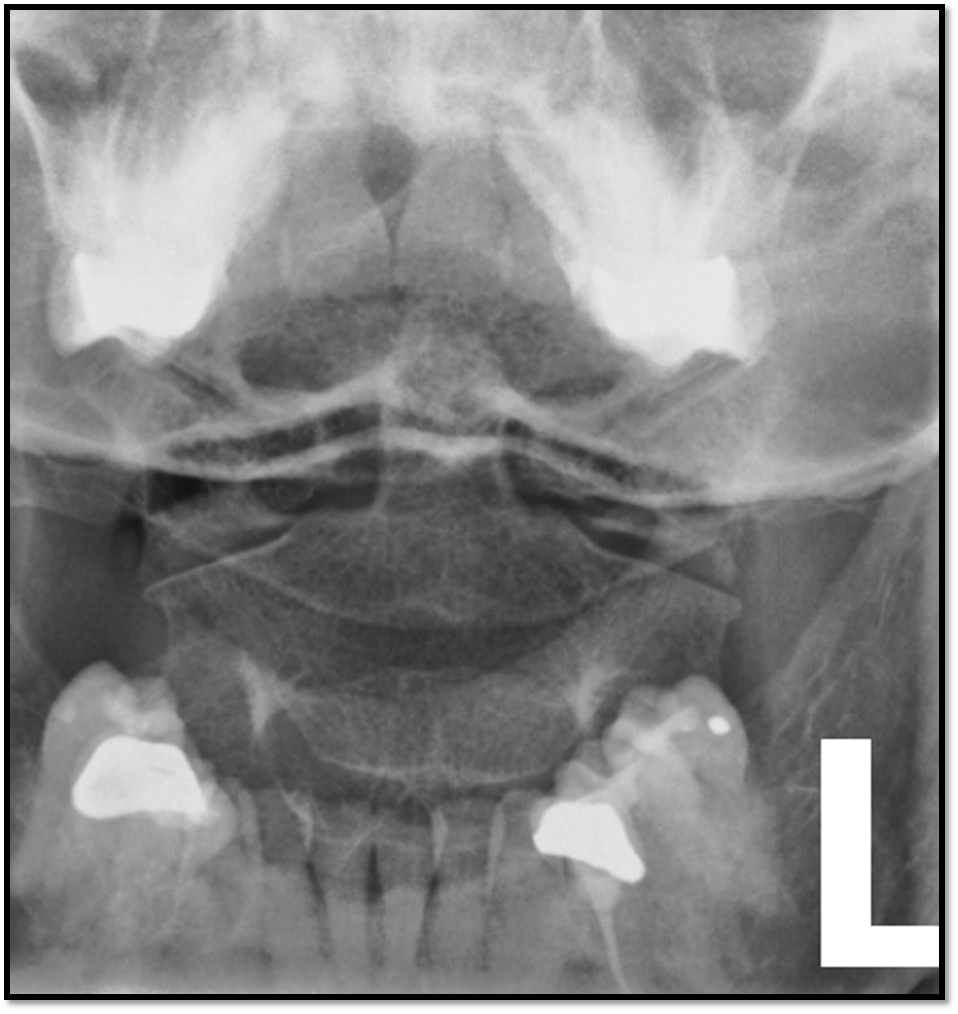

• tilt issues: double lines at zygo joints

• need to do swimmers: cant see C7 and T1

How well did you know this?

1

Q

AP Lumbar Spine

A

• spinous processes are midline

• open disc spaces

• T10-S1 included

23

pelvis is rotated in an LPO position

24

pelvis is slightly LPO and knees could be flexed to flatten spine out